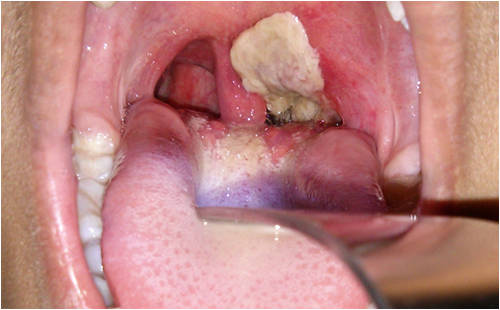

過度肥胖:過度肥胖會給盆腔肌肉施加更大的壓力,導致陰道松弛。缺乏肌肉鍛煉:缺乏盆底肌肉的鍛煉和強化,會導致陰道肌肉松弛。慢性咳嗽:長期咳嗽會增加腹壓,可能導致陰道肌肉松弛。陰道感染:某些陰道感染,如霉菌感染或細菌感染,可能導致陰道肌肉和組織受損或松弛。